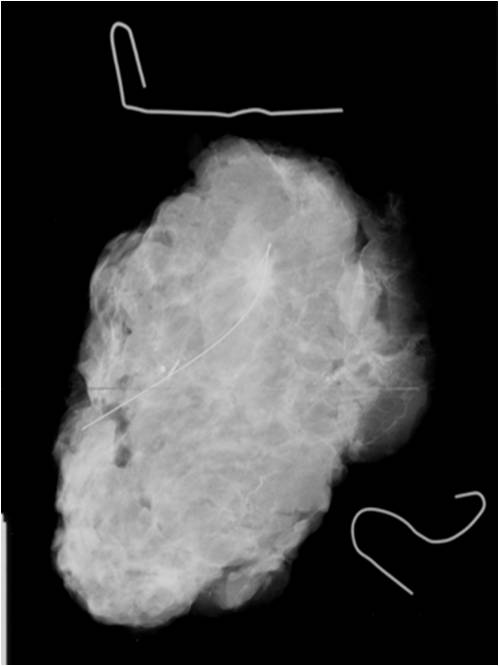

• Preoperative localization: (Picture 10.)

• Small, non-palpable tumor localization might be necessary in order to ensure optimal tissue excision.

• usually with a steel wire (hook wire or guide wire) localization. Guidance: US or X-ray.

• Localization confirmation can be performed with: specimen mammography (=mammogram taken of the removed breast part) (Picture11.)